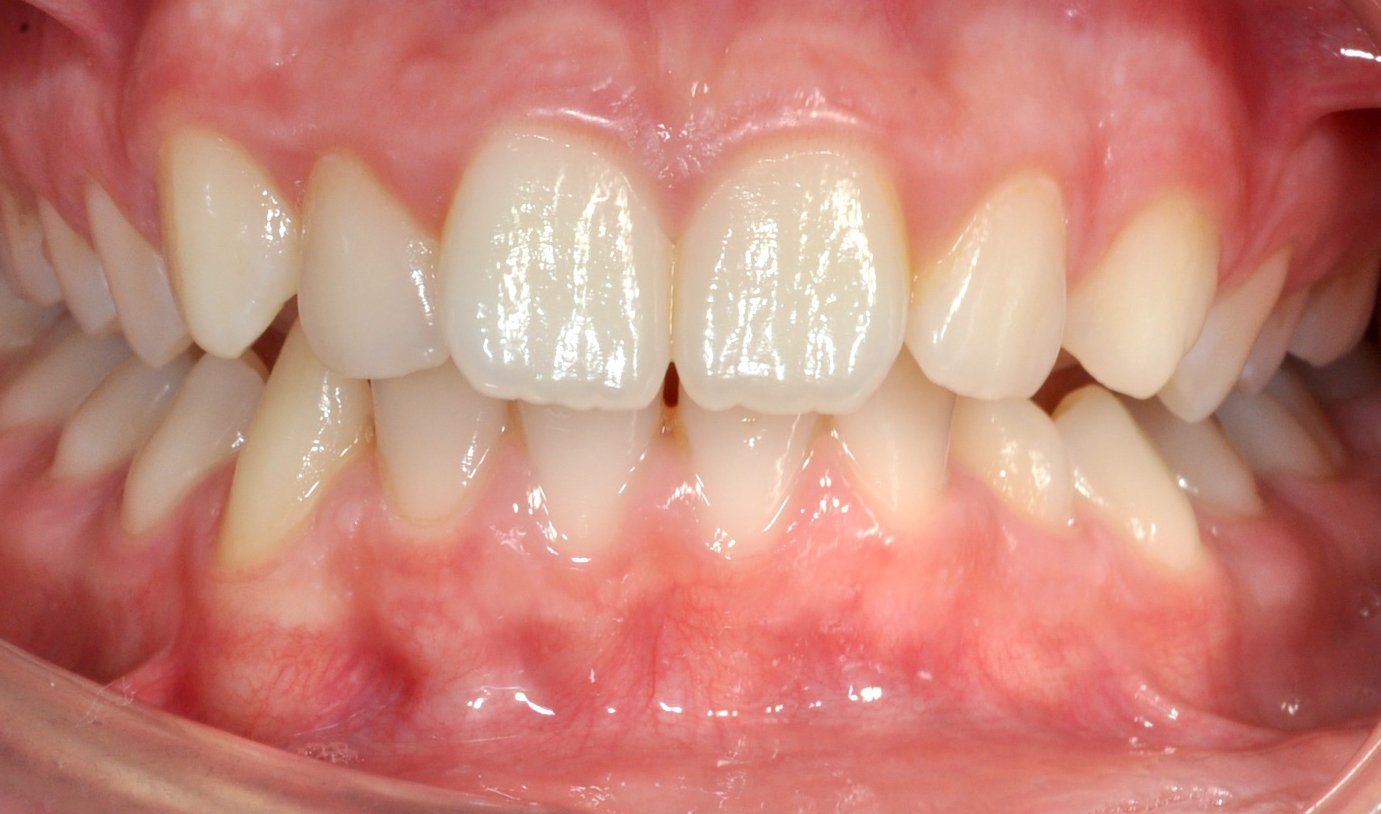

Grazie al trattamento con allineatori trasparenti, in 18 mesi è stato possibile accompagnare la crescita, correggere l’allineamento dei denti e migliorare il rapporto tra le arcate, ottenendo un sorriso più armonioso e funzionale.

DOPO